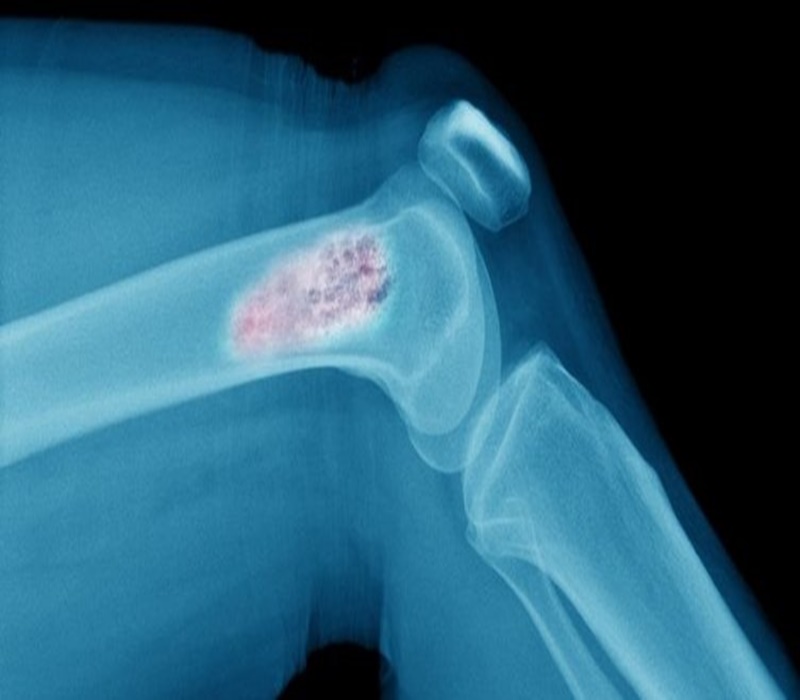

Kemik kanseri, başlangıç evresi olarak kemik hücrelerinde oluşur. Bacak ve kolda kendini gösterir, son evrelerinde doğru ciddi problemlere sebebiyet verir. Halk arasında bacak tümörleri olarak da bilinir. İlk evrede belirtileri kolay anlaşılmayan kemik kanseri, uzman bir doktora görünmenin ardından basit bir röntgenle tespit edilir. Genellikle kollarda ve bacaklardaki kemiklerde görülür kemik kanseri, bacakta uyluk kemiğinin bir bölümünde, dize yakın alt bacak kemiğinde ya da kolun omza yakın olan bölümünde sıklıkla görülür. Nadiren de olsa kalça kemiği (pelvis), omuz ya da çene gibi farklı kemiklerde de kemik kanserine rastlanır.

Kemikte en çok görülen kemik kanseri türüne "Osteosarkom" adı verilmektedir.

Osteosarkom: Osteosarkom ikinci en sık görülen kemik tümörüdür. Sıklıkla ergenlik çağında ve diz bölgesinde ortaya çıkar. Daha ender olmakla birlikte kalça ve omuz bölgesinde de görülebilir.